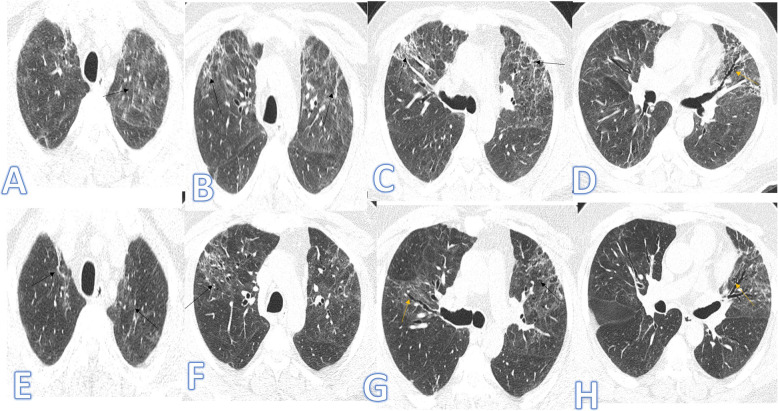

Fig. 3.

Forty-three-year-old male, he has no past medical illness; peak CT severity score 18; consolidation/crazy-paving score 14. He was admitted to the ICU; laboratory results showed lymphopenia, high CRP, d-dimer, and serum ferritin. Steroid was given; length of stay during hospitalization is 65 days. CT after 3 weeks of admission (a–d) showed bilateral GGO with bilateral upper lobe fibrotic bands (arrows) and traction bronchiectasis (orange arrows). Follow-up CT 2 months after discharge (e–h) showed lung fibrosis with parenchymal bands, coarse reticular pattern (arrows), and mild traction bronchiectasis at the anterior segments of both upper lobes (orange arrows).